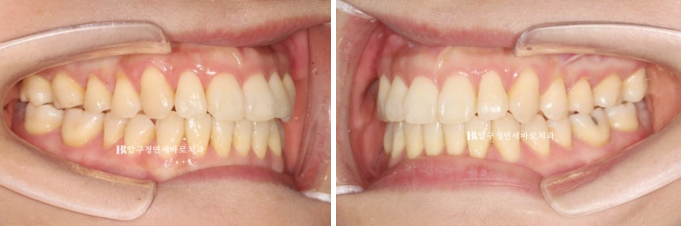

양악수술 교정을 위해 내원하신 분.

치아 중심선이 틀어져 있는 만큼 턱의 비대칭이 있고

23.01

어금니 뿐 아니라 앞니가 거꾸로 물리는 반대교합이므로 골격성 3급 부정교합으로 진단이 되었습니다.

23.01~24.07

인비절라인 투명교정과 양악수술의 조합은 좋은 결과가 나옵니다.

교정기간으로는 보통 1년 내외 생각하시면 됩니다.

이 환자분도 첫 장치를 끼신 23년 6월부터 24년 7월까지 총 1년 1개월이 걸렸고

중간에 재제작 하느라 장치를 기다리시던 한달을 빼면 실제 치료하신 기간은 1년입니다.